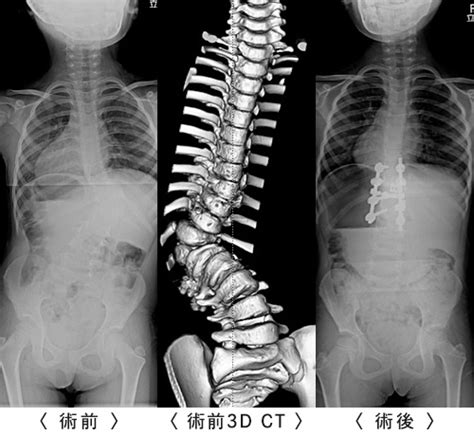

脊椎・脊髄外科領域で最も多い手術症例はこのような腰椎変性疾患です。 olifはoblique lumbar interbody fusionの略で,xlif(extreme lateral interbody fusion)とともに脊椎外科分野において、近年、革命的な進歩をもたらした手術方法です。 Chiari畸形是由於在胚胎發育時期, 小腦下部從頭的後部突出, 進入脊椎管的頸部。 其症狀通常有: 嘔吐, 頭面部肌肉無力,吞咽困難, 和不同程度的精神損害。 甚至可能發生手足癱瘓。

Chiari畸形是由於在胚胎發育時期, 小腦下部從頭的後部突出, 進入脊椎管的頸部。 其症狀通常有: 嘔吐, 頭面部肌肉無力,吞咽困難, 和不同程度的精神損害。 甚至可能發生手足癱瘓。 脊椎・脊髄外科領域で最も多い手術症例はこのような腰椎変性疾患です。 olifはoblique lumbar interbody fusionの略で,xlif(extreme lateral interbody fusion)とともに脊椎外科分野において、近年、革命的な進歩をもたらした手術方法です。

脊椎・脊髄外科領域で最も多い手術症例はこのような腰椎変性疾患です。 olifはoblique lumbar interbody fusionの略で,xlif(extreme lateral interbody fusion)とともに脊椎外科分野において、近年、革命的な進歩をもたらした手術方法です。

脊椎・脊髄外科領域で最も多い手術症例はこのような腰椎変性疾患です。 olifはoblique lumbar interbody fusionの略で,xlif(extreme lateral interbody fusion)とともに脊椎外科分野において、近年、革命的な進歩をもたらした手術方法です。 Chiari畸形是由於在胚胎發育時期, 小腦下部從頭的後部突出, 進入脊椎管的頸部。 其症狀通常有: 嘔吐, 頭面部肌肉無力,吞咽困難, 和不同程度的精神損害。 甚至可能發生手足癱瘓。 脊椎・脊髄外科領域で最も多い手術症例はこのような腰椎変性疾患です。 olifはoblique lumbar interbody fusionの略で,xlif(extreme lateral interbody fusion)とともに脊椎外科分野において、近年、革命的な進歩をもたらした手術方法です。